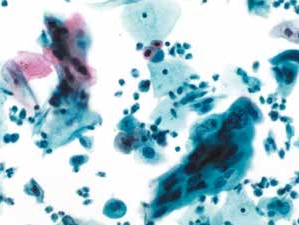

图4-11 低度鳞状上皮内病变(LSIL)(高倍、液基、巴氏染色)

细胞核增大,异型性明显,核膜不规则,染色质增粗,核质比明显增高。